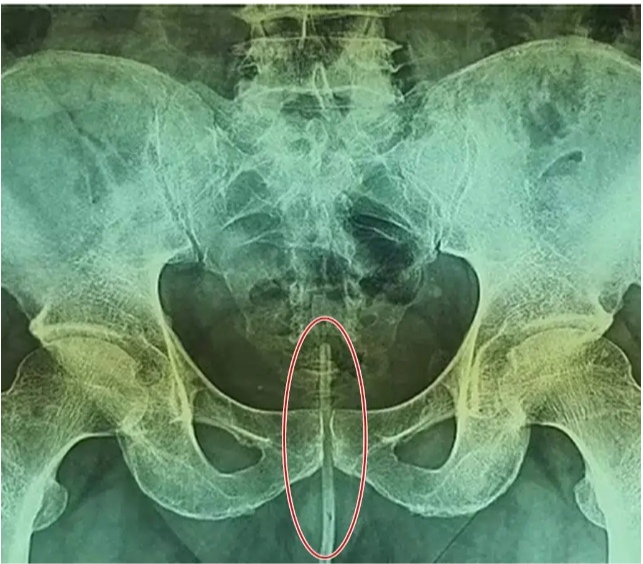

ಆದರೆ ಇದರಿಂದ ಮೂತ್ರ ಬಂದ್ ಆಗುವುದರ ಜತೆಗೆ ಆತ ಗಂಭೀರ ಸಮಸ್ಯೆಗೆ ಒಳಗಾಗುತ್ತಾನೆ. ಆ ವ್ಯಕ್ತಿಯನ್ನು ತಕ್ಷಣವೇ ಆಸ್ಪತ್ರೆಗೆ ಕರೆದೊಯ್ಯಲಾಯಿತು, ಅಲ್ಲಿ ವೈದ್ಯರು ಕಠಿಣ ಪರಿಶ್ರಮದ ನಂತರ ಶಿಶ್ನದಿಂದ ಬರೋಬ್ಬರಿ ಒಂದೂವರೆ ಅಡಿ ಉದ್ದದ, ಅಂದರೆ 18 ಸೆಂ.ಮೀ ಉದ್ದದ ಕೇಬಲ್ ಅನ್ನು ಹೊರತೆಗೆದಿದ್ದಾರೆ.

ಘಟನೆಯ ಸಂಪೂರ್ಣ ವರದಿಯನ್ನು ಆರೋಗ್ಯ ಜರ್ನಲ್ ಯುರಾಲಜಿ ಕೇಸ್ ರಿಪೋರ್ಟ್ಸ್ ನಲ್ಲಿ ಪ್ರಕಟಿಸಲಾಗಿದೆ. ವರದಿಯ ಪ್ರಕಾರ, ಪಾಕಿಸ್ತಾನದ 64 ವರ್ಷದ ವ್ಯಕ್ತಿಗೆ ಮೂತ್ರದ ಸಮಸ್ಯೆ ಇತ್ತು. ಇದನ್ನು ಸರಿಪಡಿಸಲು, ಆ ವ್ಯಕ್ತಿಯು ತನ್ನ ಮೂತ್ರನಾಳಕ್ಕೆ 18 ಸೆಂ.ಮೀ ಉದ್ದದ ತಂತಿಯನ್ನು ಹಾಕಿದನು, ಆದರೆ ಅವನು ಇದ್ರಿಂದ ಗಂಭೀರ ಸಮಸ್ಯೆಗೆ ಒಳಗಾಗಿ ಈ ಘಟನೆಯ ಬಹಿರಂಗವಾಗಿದೆ. ಪಾಕಿಸ್ತಾನದ ಈ ವ್ಯಕ್ತಿಯನ್ನು ಕರಾಚಿಯ ಅಬ್ಬಾಸಿ ಶಹೀದ್ ಆಸ್ಪತ್ರೆಗೆ ದಾಖಲಿಸಲಾಯಿತು.